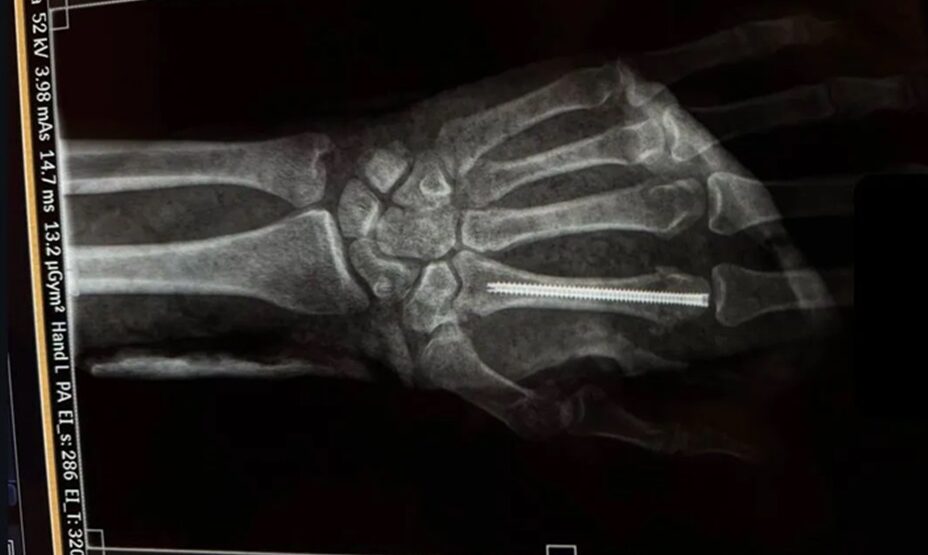

Уроженец Дагестана выложил фотографию в соцсети, из которой понятно, что спортсмену вставили штифт в кисть левой руки.